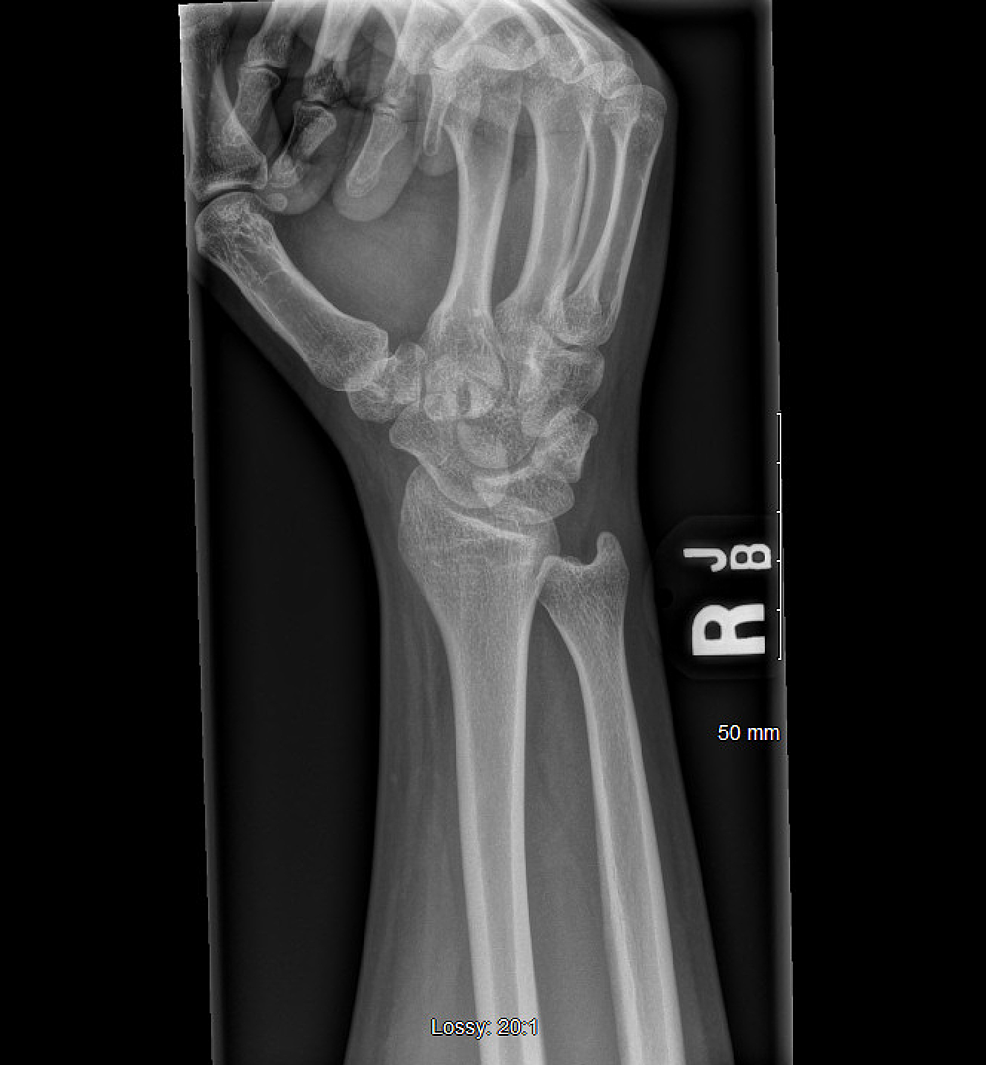

Carpal Tunnel X Ray Findings . Carpal tunnel syndrome (cts) is a collection of symptoms and signs caused by compression of the median nerve in the carpal tunnel at the wrist. Mri can detect abnormalities of the median nerve, flexor tendons, vascular structures, and transverse carpal ligament in the region of. Physical examination mainly useful for ruling out other diagnoses. Symptoms include numbness and/or tingling of the thumb and radial fingers, aching wrist, and clumsiness. Carpal tunnel compression test (durkan's test) is the most sensitive test to diagnose carpal tunnel syndrome. Cts is the most common compression neuropathy of the upper limb and is three times more common in women than men.

Cts is the most common compression neuropathy of the upper limb and is three times more common in women than men. Mri can detect abnormalities of the median nerve, flexor tendons, vascular structures, and transverse carpal ligament in the region of. Carpal tunnel compression test (durkan's test) is the most sensitive test to diagnose carpal tunnel syndrome. Carpal tunnel syndrome (cts) is a collection of symptoms and signs caused by compression of the median nerve in the carpal tunnel at the wrist. Symptoms include numbness and/or tingling of the thumb and radial fingers, aching wrist, and clumsiness. Physical examination mainly useful for ruling out other diagnoses.